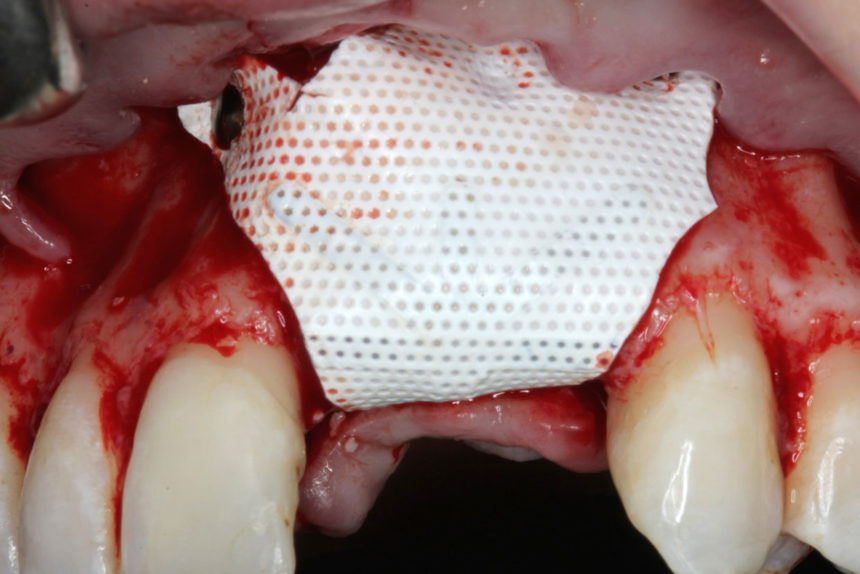

Οι συμμετέχοντες θα εξασκηθούν σε κάτω γνάθους χοίρων, με τα πιο σύγχρονα σχέδια εμφυτευμάτων, μικροχειρουργικά εργαλεία χειρός, bone tacks, βόεια υλικά πλήρωσης (filler) και απορροφήσιμες μεμβράνες και αυξητικούς παράγοντες με πλέγμα τιτανίου. Οι θεραπείες στις οποίες θα εκπαιδευτούν είναι:

1. Οριζόντια αύξηση ακρολοφίας με ταυτόχρονη τοποθέτηση εμφυτεύματος, τοποθέτηση οστικού μοσχεύματος σε στοιβάδες με απορροφήσιμη μεμβράνη & ράμματα στερέωσης

2.Οριζόντια αύξηση ακρολοφίας με τοποθέτηση απορροφήσιμης μεμβράνης, bone tacks & ανάμικτο οστικό Ξενο/Αυτο-μόσχευμα σε αναλογία 1:1

3.Κάθετη αύξηση ακρολοφίας με κυτταροπλαστικές μεμβράνες PTFE με ενίσχυση τιτανίου, οστικές βίδες & ανάμικτο οστικό Ξενο/Αυτο-μόσχευμα σε αναλογία 1:1